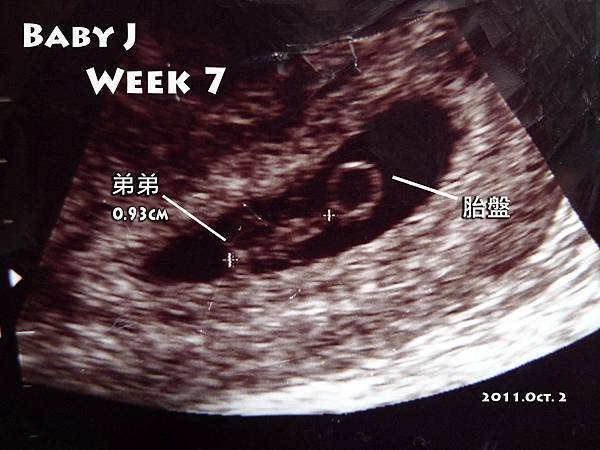

【吹媽咪懷孕日記 2】看著一點一滴的長大,很窩心 (Baby J ~Week 7)